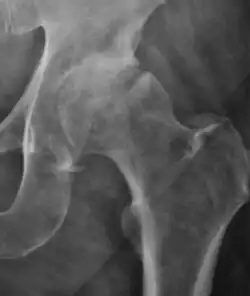

Projectional radiography ("X-ray") is the first imaging technique of choice in hip pain, not only in older people with suspected osteoarthritis but also in young people without any such suspicion. In this case plain radiography allows categorization as normal hip or dysplastic hip, or with impingement signs, pincer, cam, or a combination of both.[1]

X-Ray

Projectional radiography ("X-ray") is currently useful not only in older people in whom osteoarthritis of the hip is suspected but also in younger people without osteoarthritis, who are being evaluated for femoroacetabular impingement (FAI) or hip dysplasia.[1]

Plain radiography allows us to categorize the hip as normal or dysplastic or with impingement signs (pincer, cam, or a combination of both). Besides these, pathologic processes like osteoarthritis, inflammatory diseases, infection, or tumors can also be identified (Figure 1).[1]

Figure 1.

-

Radiography in normal hip -

X-ray in pincer impingement type of hip dysplasia -

X-ray of cam -

Hip in osteoarthritis -

Septic arthritis

X-ray in pediatrics